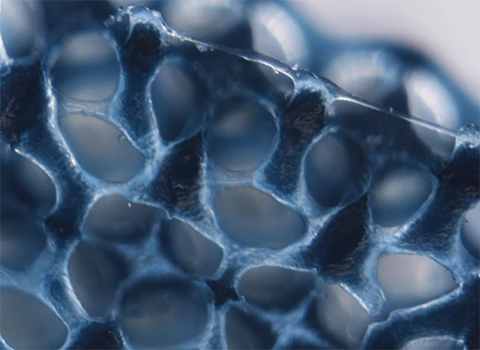

La ingeniería regenerativa es un campo nuevo y emocionante que se define como la convergencia de los avances en la ciencia e ingeniería de materiales, células madre y biología del desarrollo, ciencias físicas y la aplicación clínica para desarrollar herramientas escalables y confiables que permitan la regeneración ó reconstrucción de tejidos complejos y órganos. Puede considerarse un campo que busca facilitar la implementación de la medicina regenerativa para todos.

Con este objetivo, profesores de la Escuela de Ingeniería McCormick y de la Escuela de Medicina Feinberg convergen para participar en investigaciones y educación a través del Instituto Querrey Simpson de Ingeniería Regenerativa de la Universidad Northwestern (QSI RENU), que liderará la iniciativa para desarrollar y traducir tecnologías transformadoras que capaciten a nuestro cuerpo para sanar.